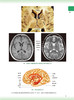

头颈部放射治疗解剖图谱 第2版 附音频 罗i京伟 罗德红 头颈部解剖知识临床肿瘤放射治疗 大体解剖CTMRI影像资料 人民卫生出版社

内容提要: